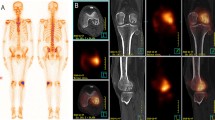

Scintigraphy revealed 44 metastases in 59 patients (sensitivity, 70%; specificity, 94%; positive predictive value, 95%). Bone scintigraphy detected 44 lesions that fulfilled the criteria of a metastatic deposit. Of the 44 lesions, 36 (82%) were located in the axial skeleton and 8 (18%) in the extremities, ribs, sternum. A total of 29 lesions were considered as of uncertain origin (grade 2), and 26 lesions were regarded as definitely benign (grade 1). About 5 lesions were graded as grade 2 in scintigraphy, while MRI graded them as degeneration or benign compression (Grade 1) (Fig. 1). For 11 lesions the same grade was regarded in both MRI and scintigraphy (3 lesion grade 3; 2 lesion grade 2; 6 lesion grade 1) (Fig. 2). Two lesions graded as grade 3, and 11 lesions graded as grade 2 in scintigraphy demonstrated no pathological signal intensity in MRI (Fig. 3). A total of 18 lesions with no activity in scintigraphy were graded as grade 3 lesions in MRI. In pelvic region the number of MRI grade 3 lesions was 25, while in scintigraphy it was 3. The 17 lesions depicted in sacrum, pubis, and ischion in MRI demonstrated no activity in scintigraphy.

A 62 years old female with back pain operated 5 years ago for right breast cancer. Whole-body scintigram (anterior view) (a) shows metastatic activity increase in D8 vertebrae (arrow) MR images shows height loss in the D8 vertebrae body, T1 hypointense (b), STIR hyperintense, and (c) pathological signal changes (arrows). Note almost complete regression of the pathological signal changes in the follow-up MR images after 45 days (d) due to benign osteoporotic compression fracture (arrow)

A 63 years old female operated 4 years ago with left breast cancer. Whole-body scintigram shows suspect activity increase in the right sternoclavicular region. In the sagittal T1 (b) and STIR (c) weighted MR sequences for the dorsolumbar region depicts T1 hypo-STIR hyperintense metastatic lesions in the dorsal and lumbar vertebrae (arrows). In the coronal T1 (d) and STIR (e) weighted sequences for the pelvis, multiple T1 hypo-STIR hyperintense metastatic lesions in the right side of the sacrum, ilium, and ischium, intertrochanteric region of the right femur and the left collum femoris (arrows)